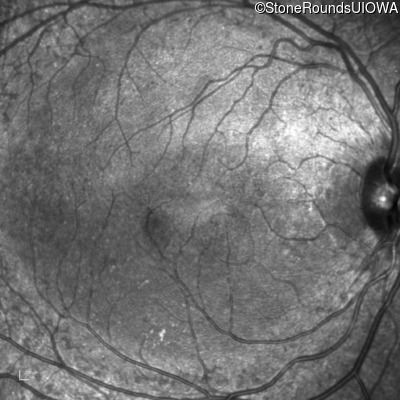

Infrared Fundus Photograph - Right - 20/25 -1

Exemplar